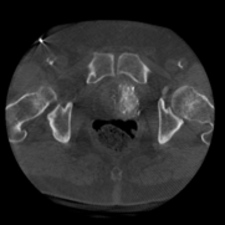

Die Prostataarterienembolisation ist ein schonendes, minimal-invasives Verfahren zur Behandlung einer vergrößerten Prostata (benigne Prostatahyperplasie, BPH).

Dabei werden gezielt kleine Blutgefäße, die die Prostata versorgen, mithilfe winziger Partikel verschlossen. Dadurch schrumpft das Prostatagewebe und die Beschwerden wie häufiges oder erschwertes Wasserlassen lassen nach.

Die Prostataarterienembolisation bietet einen Erhalt der Sexualfunktion und einen kurzen Krankenhausaufenthalt.